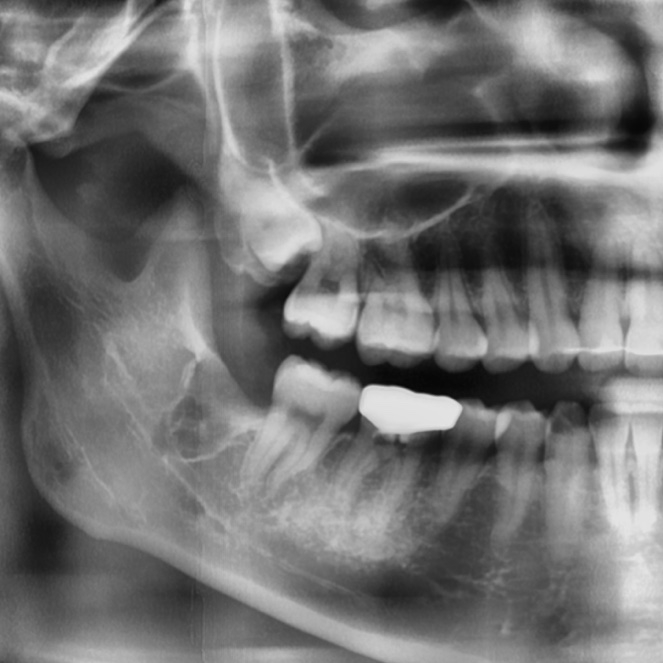

사랑니는 크게 일반 자연치아처럼 정상적으로 자리를 잡으며 나는 정상사랑니, 누운 형태로 자라 절반 정도만 잇몸을 뚫고 나온 반매복사랑니, 애초에 잇몸을 뚫고 나오지 못한 채 잇몸 안에서 자라는 매복사랑니 3가지 형태로 나눌 수 있습니다.

그 중에서도 사랑니는 반매복 사랑니인 경우가 많은데요. 반매복 사랑니는 완전한 매복사랑니보다 잇몸염증을 유발하거나 인접치아를 손상시키는기 더 쉽기 때문에 사랑니발치를 하는 것이 현명합니다.

반매복 또는 매복사랑니의 경우에는 단순히 발치만으로도 제거되기 보다는 잇몸 절개를 해야하는 등의 난도 높은 시술이 필요할 수 있기에 반드시 약수치과 전문의와의 충분한 상담을 통해 진행하셔야 하는데요.

또한 약수치과 바른영치과는 사랑니발치 시 느끼게 될 통증에 대한 두려움에 통증이 심함에도 불구하고 사랑니발치를 미루고 있는 환자분들을 위하여 3단계 마취시스템을 통해 통증에 대한 두려움을 줄여드리고 있으며, 환자의 사랑니 형태를 면밀히 관찰 후 치료를 도와드릴 수 있도록 3D-CT 등 정밀진단장비를 보유하고 있습니다.